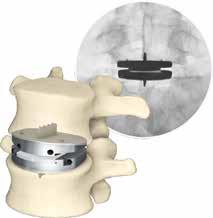

TOTAL DISC REPLACEMENT? TOTAL DISC

Total disc replacement (TDR) may be an alternative to spinal fusion for patients with cervical or lumbar herniated discs or degenerative disc disease.

The goals of total disc replacement surgery are to maintain segmental spinal motion, relieve pain, increase activity, restore disc height and proper spine curvature, and reduce post-operative recuperation time.

If you are experiencing neck or back pain and are considering surgery, isn't it worth your time to schedule an appointment with Dr. Jason E. Garber to nd out if motion preservation technology is an option for you?

Dr. Garber is one of Southern Nevada's most experienced spinal surgeons and a leader in arti cial disc replacement surgery.